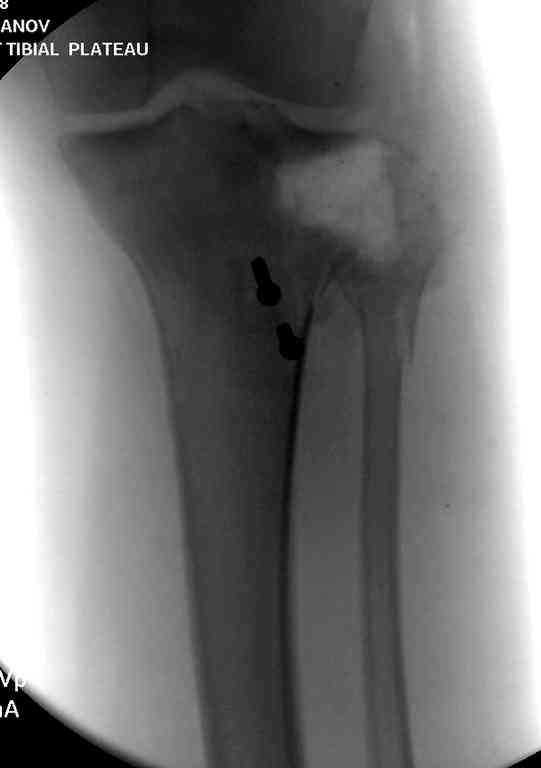

Пожалуйста, снимки.

Коллеги фиксатор Numelock II

На вашем снимке из-за ротации трудно угадать положение пластины, и желательно сделать снимок с захватом верхнего участка бедра.

Одинокий кортикальный шуруп не удержит тибиальный бугор, сустав тибиал плато оставлен без репозиции и фиксации.